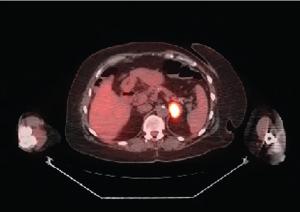

A 48-year-old Caucasian woman presented with a palpable right breast mass. Physical examination confirmed a lump on the upper outer quadrant of her right breast. On PET/CT scan there was an incidental finding of increased metabolic activity in the left lateral breast.